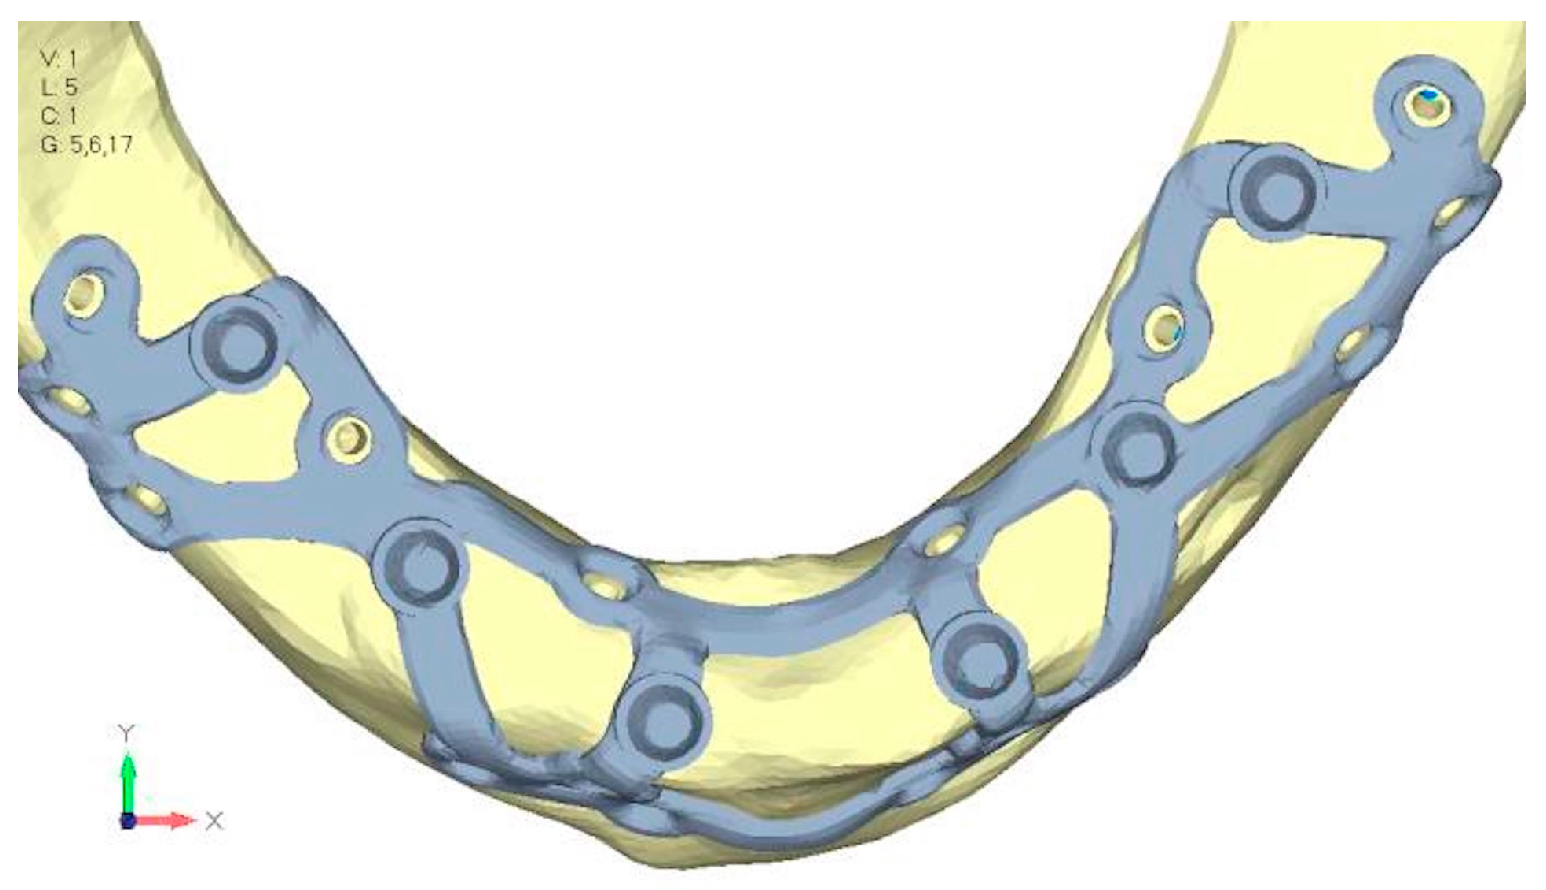

- Model V0. This model represents the initial analysis performed on the lower arch. The implant consists of two completely separate hemi-arches. The situation observed in the lower model is very similar to that found in the upper model. The most significant load is load 3 (Figure 20a,b), corresponding to chewing in the anterior right sector. Loads distributed over larger areas, such as configurations 1 and 2, result in less stress on both the implant and the bone (Figure 21 and Figure 22).